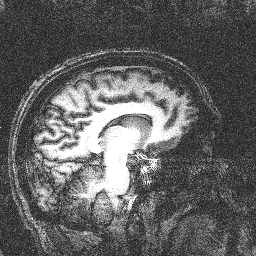

Sagittal Slice

These are MRI (Magnetic Resonance Imaging) scans of my brain obtained at Brookhaven National Laboratory in 1999. I was a volunteer in a study attempting to correlate brain activity and variable hand gripping strength. My brain showed no activity, but I did learn the meaning of manipulandum.

They actually had trouble shimming my head... I am not kidding, this is what they told me. At one point, my head was misaligned so it appeared as if I had a big hole in my brain. All possible jokes have already been made on this last point...